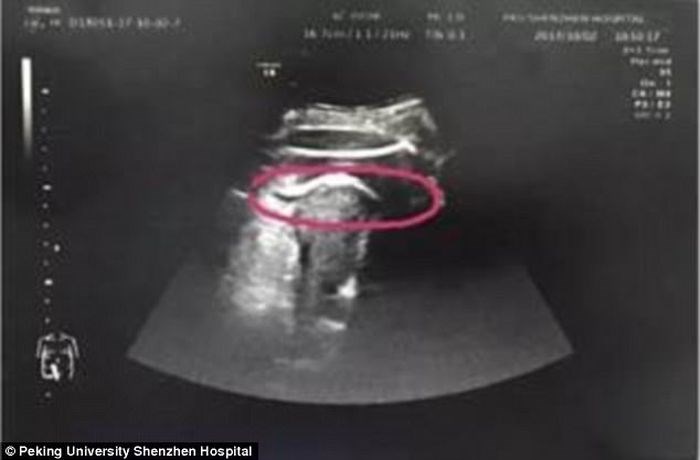

Bebê ainda no ventre, dá chute tão forte que perfura útero da mãe

12/10/2017 às 08h08